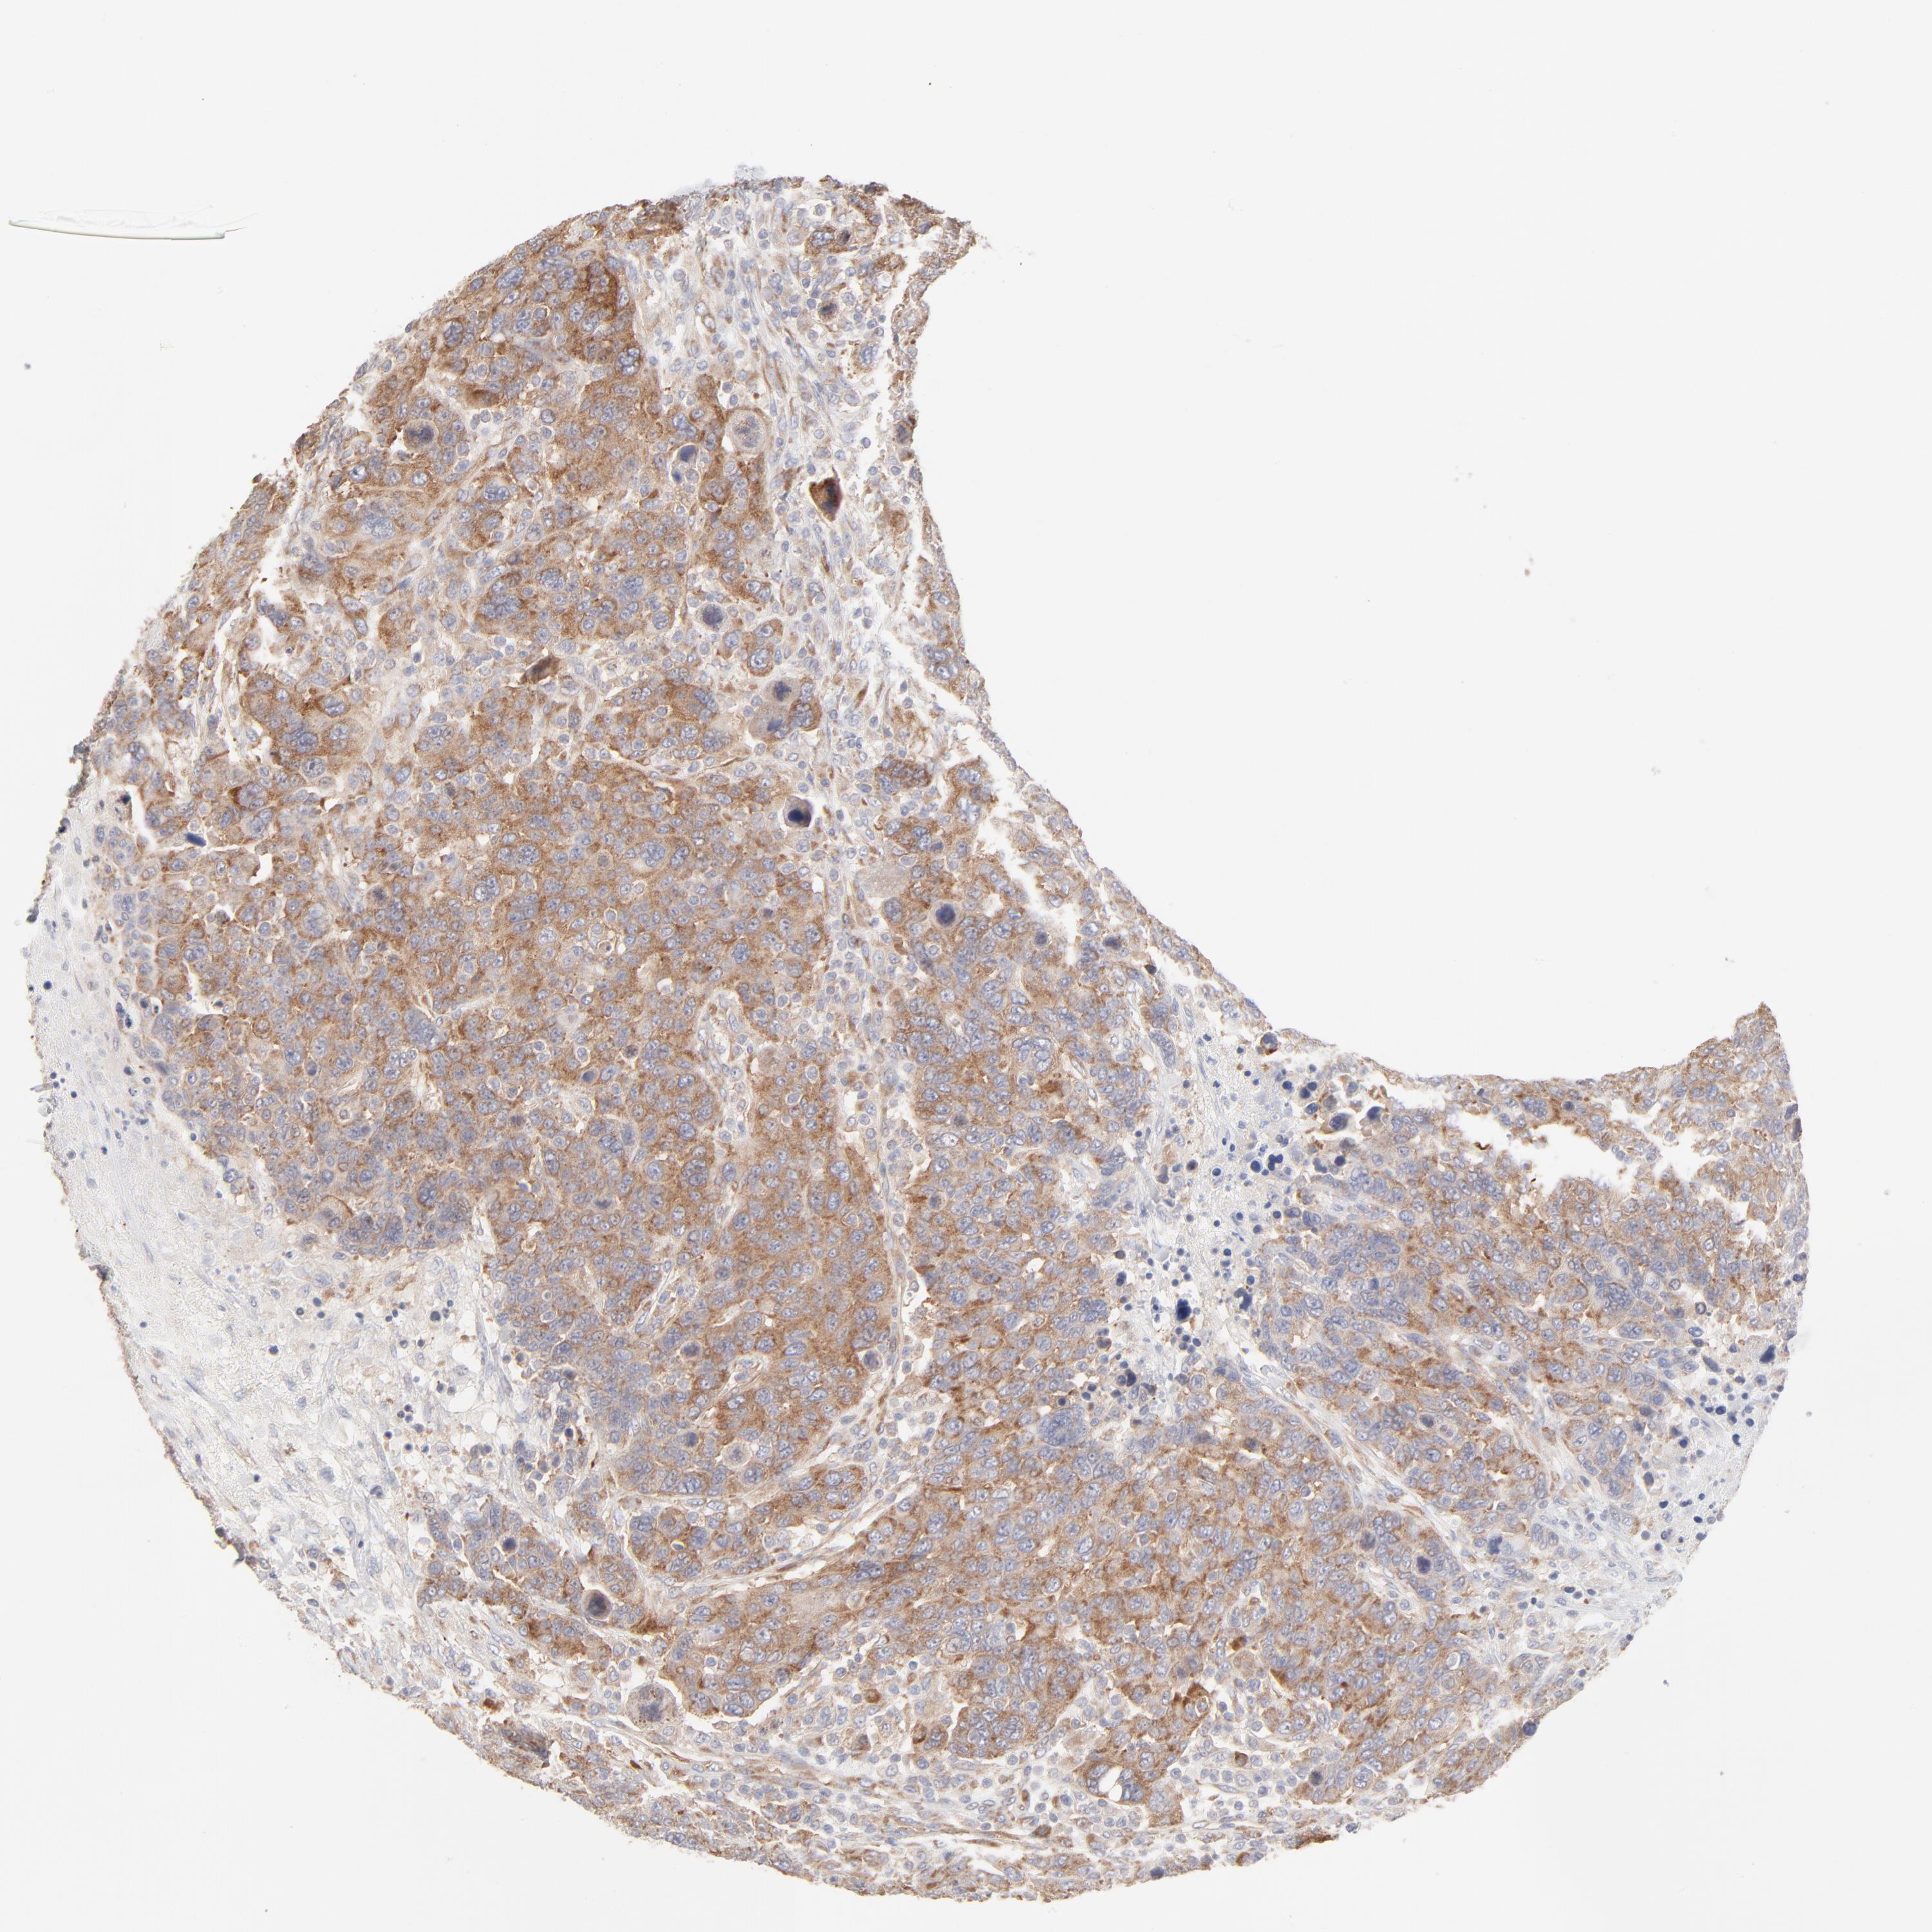

CANCER BREAST CANCER Show tissue menu

BRCA TCGA BRCA VALIDATION PROTEIN EXPRESSION

Breast cancer

Human cancer